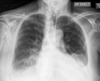

**Heart failure** Alveolar batwing shadowing Kerley B lines Cardiomegaly Upper lobe Diversion Pleural Effusion